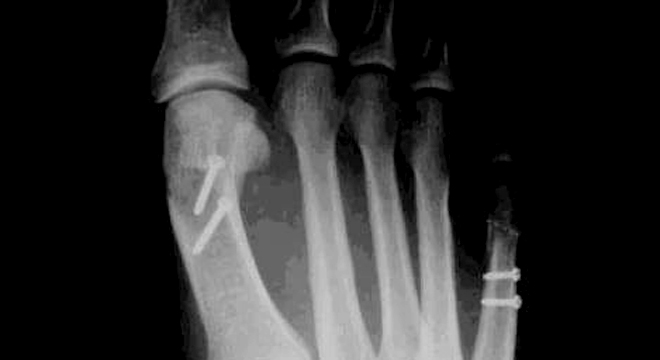

Hallux valgus im Röntgenbild

Das Röntgenbild sichert die Diagnose durch die sichtbare Aufspreizung des Mittel- und Vorfusses und die Abweichung der Grosszehe.